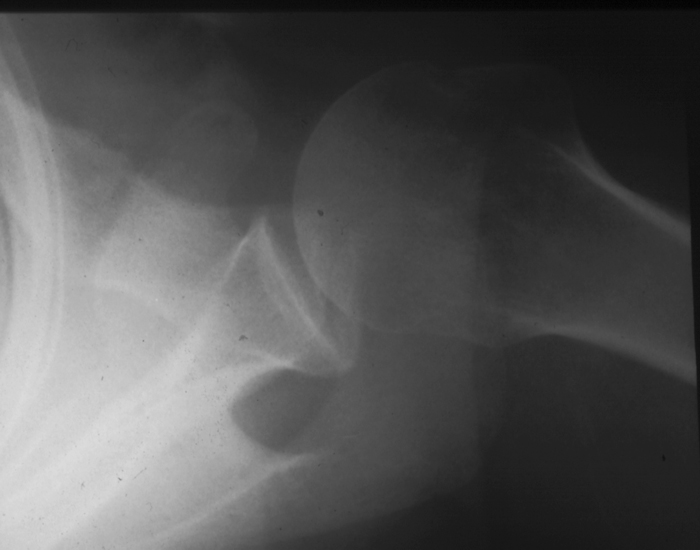

Radiology MS 29 - Normal Shoulder

Identify: clavicle, acromion, corocoid process, glenoid, humeral head